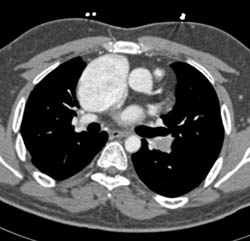

Diagnosis

Large Right Atrium